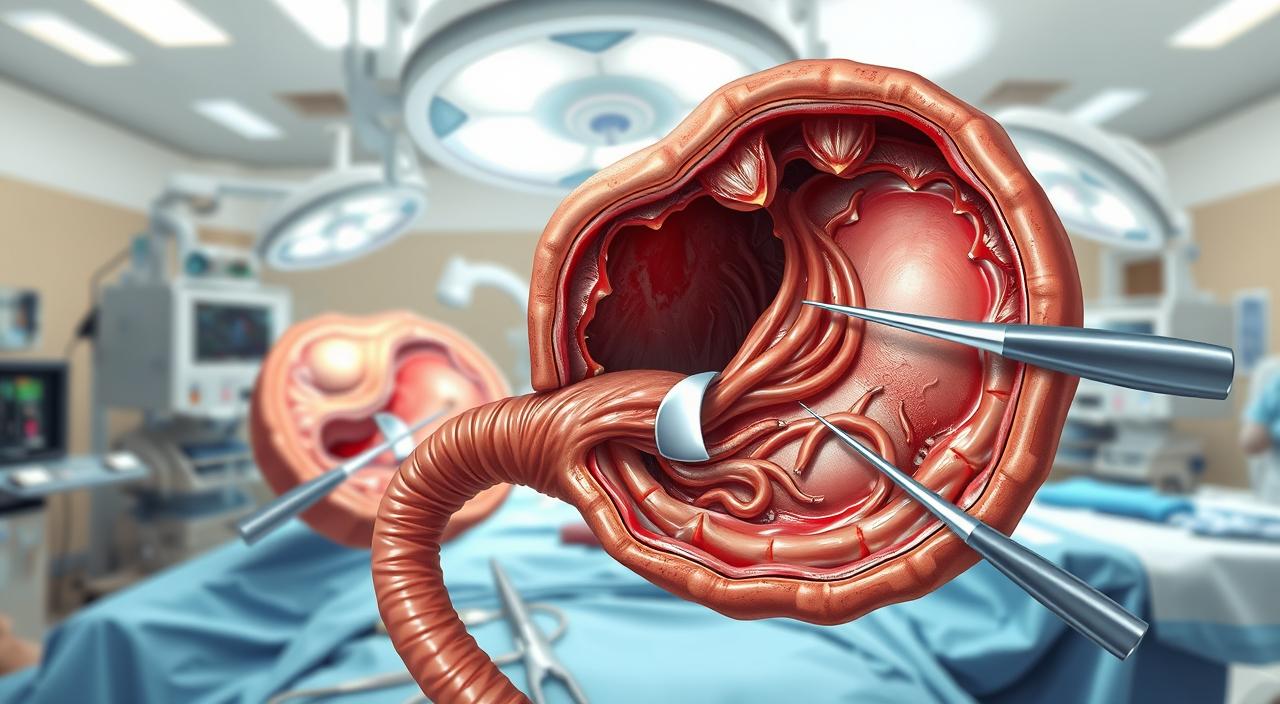

Como a colecistectomia é feita na prática

Na prática clínica, a remoção da vesícula costuma seguir protocolos que privilegiam técnicas minimamente invasivas.

Videolaparoscopia: passos essenciais

O procedimento inicia com pequenas incisões no abdômen. Através delas entra uma câmera e instrumentos finos.

O cirurgião visualiza o órgão na tela, identifica o pedículo e realiza a retirada com mínimo trauma. As incisões geram cicatrizes pequenas e menos dor pós-operatória.

Quando a técnica aberta é necessária

Em casos complexos ou inflamação intensa, a incisão subcostal amplia o acesso. Essa técnica permite controle direto e é indicada quando a laparoscopia não é segura.

Robótica e colangiografia intraoperatória

A cirurgia robótica aumenta precisão e reduz tremor em situações selecionadas. A colangiografia intraoperatória mapeia as vias biliares e ajuda a detectar cálculos no colédoco, diminuindo complicações.